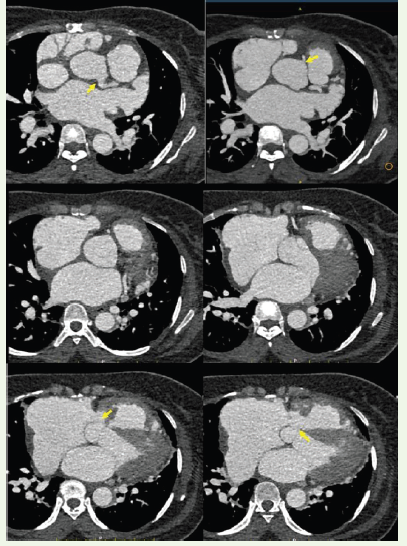

Figure 2:Serial axial ECG-gated contrast-enhanced CT images obtained in craniocaudal sequence through the aortic root. The superior sections demonstrate the right coronary ostium and left coronary ostium arising normally from their respective coronary sinuses (arrows). The inferior sections show focal aneurysmal dilatation of the non-coronary sinus with protrusion.

CT angiography demonstrated a focal aneurysmal dilatation

arising from the non-coronary sinus of Valsalva, measuring

approximately 18 × 14 mm. A well-defined rupture defect measuring

approximately 12.5 × 11.4 mm was identified in the wall of the

aneurysmal sac. Through this defect, contrast was seen directly

opacifying the right atrium, confirming the presence of a fistulous

communication.The aneurysmal sac was noted to protrude into the right atrium, producing indentation of the adjacent tricuspid valve leaflet. There was significant dilatation of the right atrium and inferior vena cava, with associated hepatic venous congestion. The main pulmonary artery was dilated, measuring approximately 3.9 cm, suggestive of pulmonary hypertension. Mild pericardial effusion and cardiomegaly were also present.

The right and left coronary sinuses were unremarkable. The coronary arteries, thoracic aorta, and abdominal aorta were within normal limits.